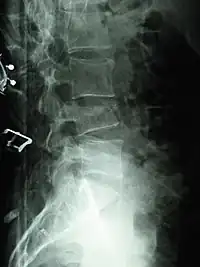

Compression fracture of the fourth lumbar vertebra post falling from a height.

X-ray of the lumbar spine with a compression fracture of the third lumbar vertebra.

A compression fracture is a collapse of a vertebra. It may be due to trauma or due to a weakening of the vertebra (compare with burst fracture). This weakening is seen in patients with osteoporosis or osteogenesis imperfecta, lytic lesions from metastatic or primary tumors,[1] or infection.[2] In healthy patients, it is most often seen in individuals suffering extreme vertical shocks, such as ejecting from an ejection seat. Seen in lateral views in plain x-ray films, compression fractures of the spine characteristically appear as wedge deformities, with greater loss of height anteriorly than posteriorly and intact pedicles in the anteroposterior view.[3]

Compression fractures are usually diagnosed on spinal radiographs, where a wedge-shaped vertebra may be visible or there may be loss of height of the vertebra. In addition, bone density measurement may be performed to evaluate for osteoporosis. When a tumor is suspected as the underlying cause, or the fracture was caused by severe trauma, CT or MRI scans may be performed.